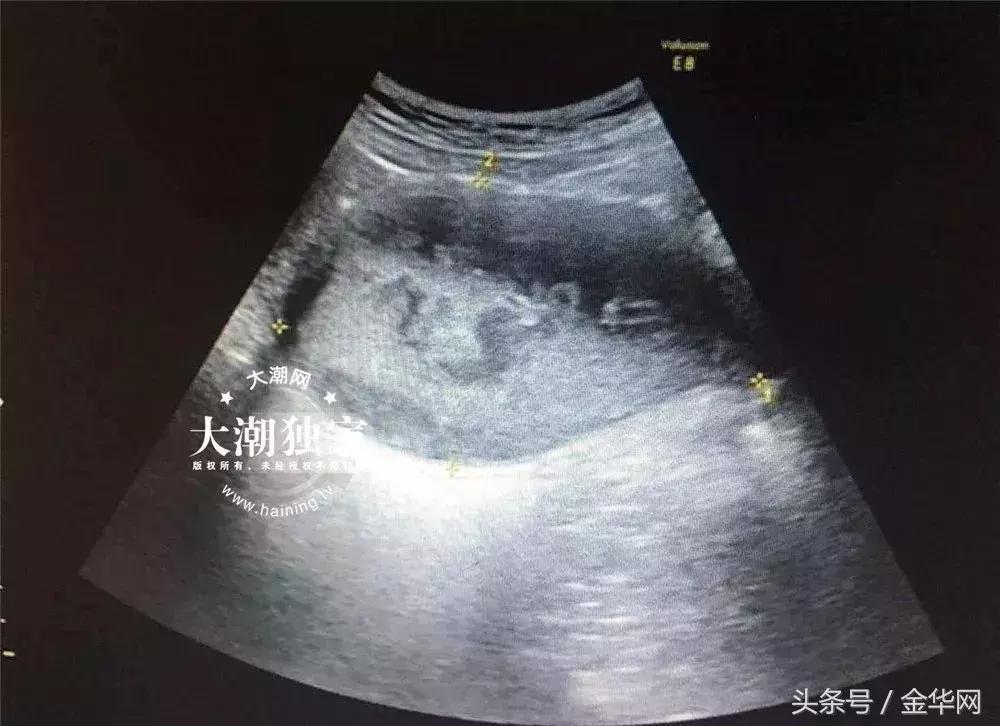

接诊的医生询问了小燕的病情后,当场就觉得小燕的情况有些特别,于是马上给小燕安排了B超和妇科检查。

△小燕的B超报告

根据检查,医院妇科主任俞丽娟判断,小燕得了处女膜闭锁伴盆腔感染!需要马上住院进行手术治疗。

那么,什么叫处女膜闭锁?大潮君得知,正常女性的处女膜上是有小孔的,这些小孔是经血排出体外的通道。如果处女膜上没有小孔,那就是处女膜闭锁了。经血无法从体内排出,逐渐堆积,就会造成阴道子宫积血,这就是小燕产生臭味以及周期性下腹痛的原因所在。